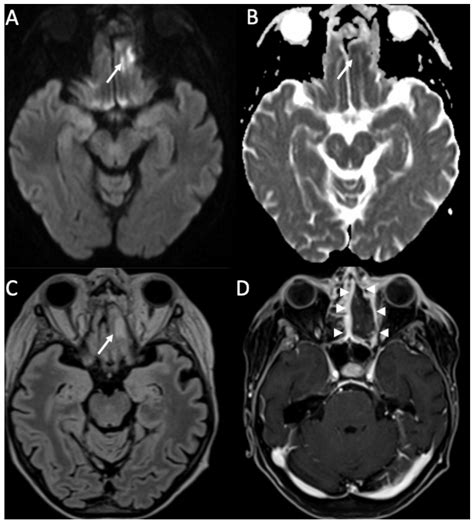

Diagnosing encephalitis involves a combination of clinical evaluation, laboratory tests, and imaging studies. The diagnostic process typically includes:

• Imaging Studies: Magnetic resonance imaging (MRI) and computed tomography (CT) scans to visualize brain inflammation and rule out other conditions.

Diagnosing meningitis involves a combination of clinical evaluation, laboratory tests, and imaging studies. The diagnostic process typically includes:

• Imaging Studies: Magnetic resonance imaging (MRI) and computed tomography (CT) scans to visualize inflammation and rule out other conditions.